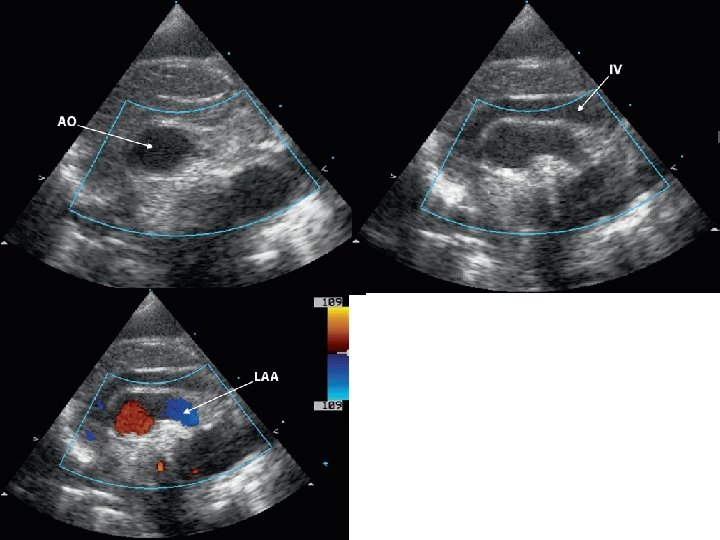

Cervical aortic arch

Cervical arch-different types